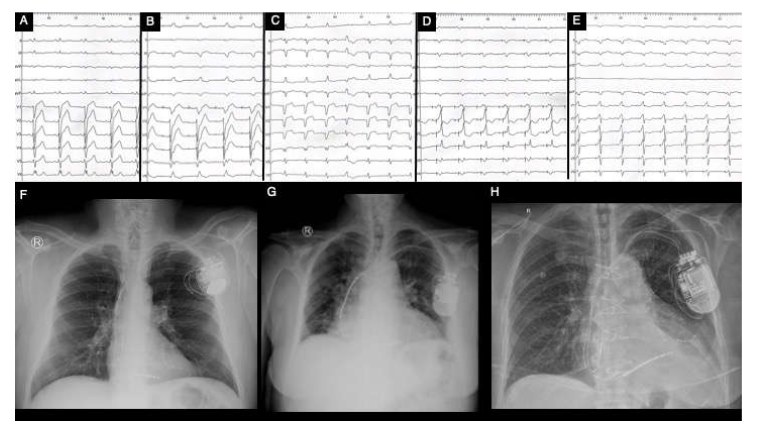

On the other hand, advanced multimodal imaging plays a paramount role in diagnosing and risk stratifying of these patients, especially by the joint use of echocardiography and cardiac magnetic resonance imaging (CMR) [27]. Both European Society of Cardiology (ESC) and American Heart Association/American College of Cardiology (AHA/ACC) guidelines recommend standard transthoracic echocardiography (Figure 1) as the first-encounter imaging tool in patients suspected of HCM because it can provide a significant overview about LV hypertrophy, LV systolic and diastolic function, LVOT or intraventricular dynamic obstruction and mitral valve phenotypic particularities [28,29,30]. Echocardiographic findings in patients with HCM are described in Table 1 [27,28,31].

Figure 1. Echocardiographic findings in hypertrophic cardiomyopathy. TTE: obstructive HCM (Maron type III) in PLAX (A) and PSAX (B) views with an IVS of 23 mm and a ILW of 19 mm, with SAM of MV’s anterior leaflet in PLAX M-Mode (C) and a LVOT gradient of 127 mmHg and velocity of 5.65 m/s (D); contrast transthoracic echocardiography of a HCM with mid-cavity obstruction and apical LV aneurysm in A4C in systole (E) and diastole (F); HCM (Maron type IV) with isolated hypertrophy (18 mm) of the apical segment of LV’s lateral wall (G, H); non-obstructive HCM (Maron type II) with isolated hypertrophy of the IVS (20 mm) (I); obstructive HCM with SAM of the MV’s anterior leaflet and of its chordae tendineae with leads to severe MR (JL). TEE: obstructive HCM with SAM of MV’s anterior leaflet—A2 scallop (MO). Abbreviations: A4C, apical four-chamber view; HCM, hypertrophic cardiomyopathy; IVS, interventricular septum; LV, left ventricle; LVOT, left ventricle outflow tract; MV, mitral valve; PLAX, parasternal long-axis view; PSAX, parasternal short-axis view; SAM, systolic anterior movement; TEE, transoesophageal echocardiography; TTE, transthoracic echocardiography.